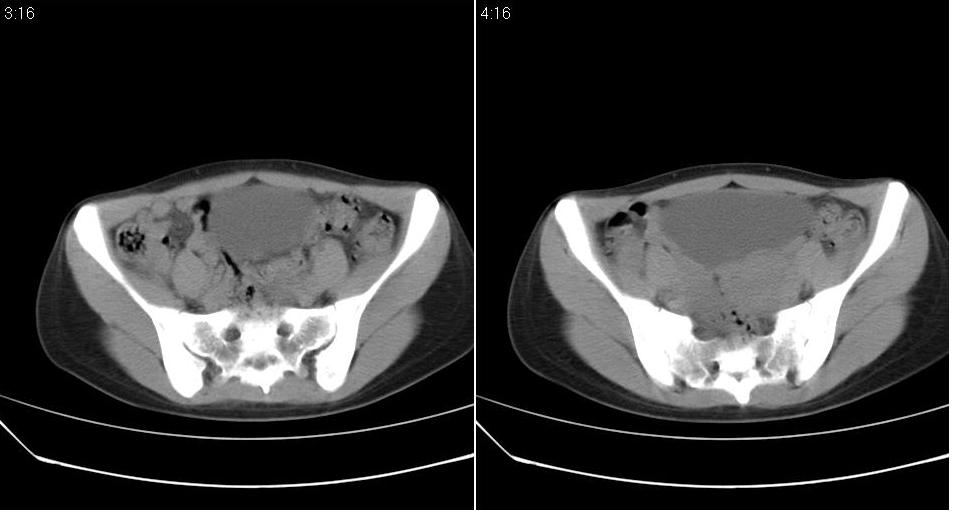

标题: CT22811:女 36岁,B超提示右侧附件囊性占位。 [打印本页]

标题: CT22811:女 36岁,B超提示右侧附件囊性占位。

右侧卵巢囊肿

右侧卵巢囊肿。

支持右侧附件良性囊性占位性改变。

手术结果证实为右侧输卵管囊肿。

输卵管囊肿罕见,从影像上无法同卵巢囊肿区分。

还是报右侧附件区良性囊性占位性改变       至于输尿管或卵巢囊肿不太好鉴别